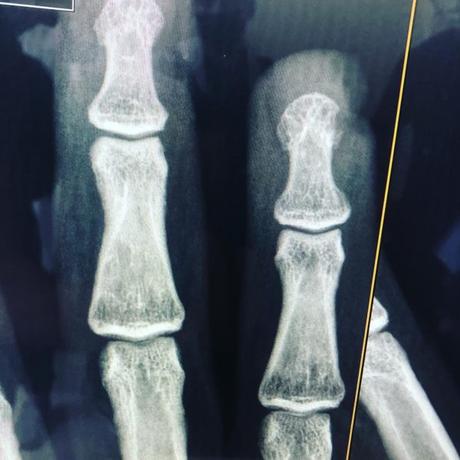

Herida cortante con sierra eléctrica / fractura expuesta de falange / colgajos de avance e injerto cutánea